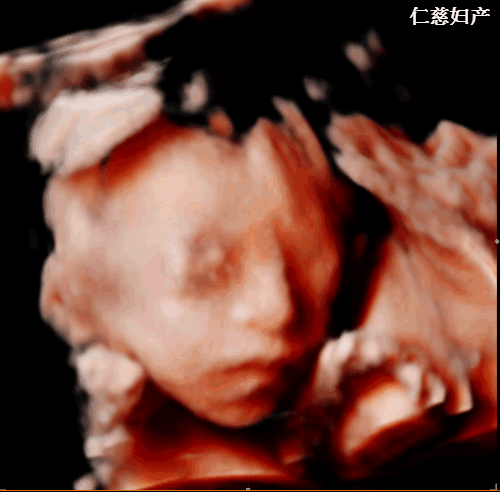

四維彩超

便是諸多次孕檢中具有里程碑意義的一步!

四維彩超的全稱是四維彩色超聲診斷儀,能夠多方位、多角度地觀察宮內(nèi)胎兒的生長發(fā)育情況,為早期診斷胎兒先天性體表畸形和先天性心臟疾病提供準(zhǔn)確的科學(xué)依據(jù)。

四維彩超排畸篩查,最佳時間一般在20-24周,因?yàn)檫@個時間段,胎兒肢體及主要臟器已發(fā)育,且羊水較多、胎兒活動度較大,局部結(jié)構(gòu)和運(yùn)動形態(tài)比較清晰。

(仁慈婦產(chǎn)四維彩超實(shí)拍圖)